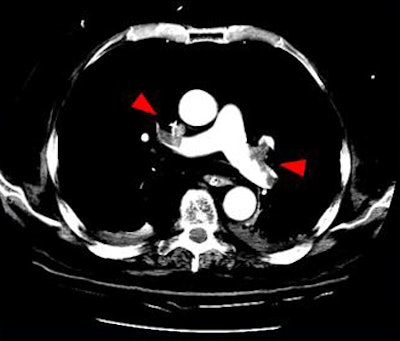

| Above, small filling defects, or dots, may represent normal embolic activity originating from the lower-extremity venous valve cusps. Below, location of dots in 27 of 101 patients diagnosed with PE in the study population. |

"We proposed a theory that dots are small focal and rounded filling defects in the peripheral pulmonary arteries," Suh said. They have a dotlike appearance and are uniformly noted to have blood flowing around them except in the most terminal branches. They are not associated with detectable clot load in lower extremities, she said.

"Dots are not clots in the traditional sense, and we hypothesize that dots represent perhaps normal embolic activity originating from the lower extremity veins."